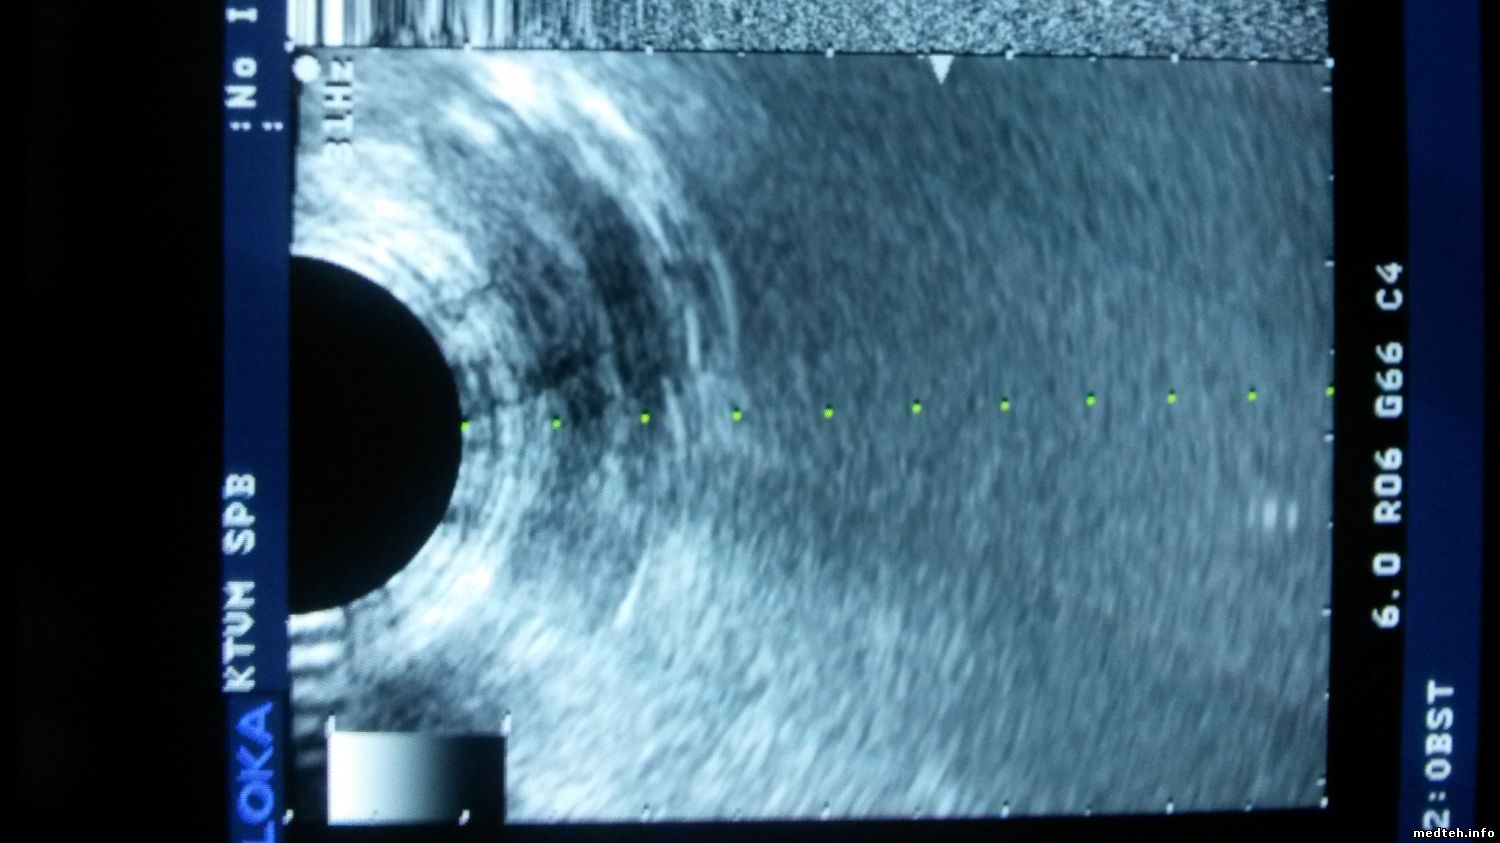

Доброго времени суток, господа. Я не медтехник, я врач хирург. В настоящее время занимаюсь частной практикой на аппарате ALOKA SSD-4000, в небольшом (язык не поворачивается) медцентре. Аппарат мой собственный, купил 4 года назад, б/у со всеми датчиками. За все время использования пользовался только конвексным и линейным и то раз 7-10 в месяц по 2-3 часа. Супруга отучилась по УЗ диагностике и ей, в рамках ее профессии (гинеколог) потребовалась работа с ректовагинальным датчиком. Но вот проблема. очень плохая визуализация чего либо, на разном увеличении, при переключении всех режимов и тп с этим датчиком, плюс от "полукруга" датчика (на экране) темные полосы разной ширины. Подскажите пожалуйста сервис в СПб, который смог бы провести диагностику датчика и вынести вердикт.

Датчик UST-9124

9886951.jpg (92.4 Kb)